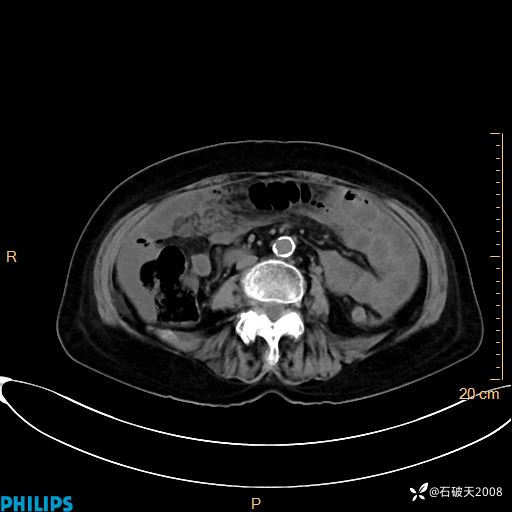

动脉期